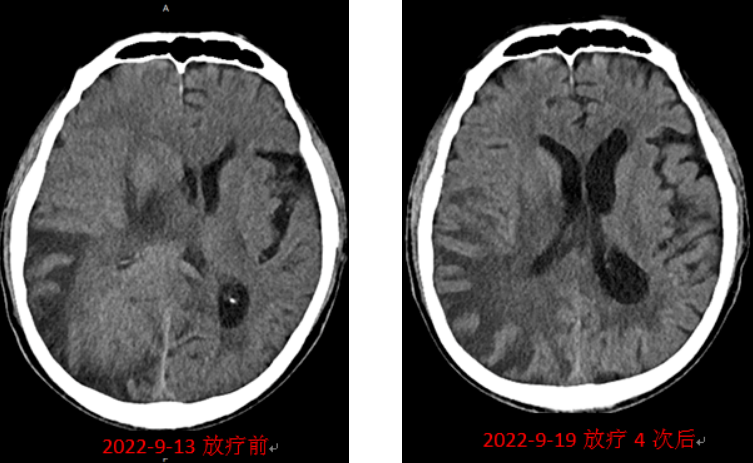

经充分准备后,于9月14日开始放疗,放疗4次后复查头颅CT可见颅内占位明显缩小,右侧脑室显现,该肿块对放射线敏感度高,进一步印证了颅内淋巴瘤的诊断。老人状态也逐渐变好了,照顾他的护工惊喜地发现,老人左侧肢体也慢慢地能动了,能拉着床栏杆抬头、欠身了,抱老人下地时腿能使劲儿了,慢慢地能说几个字、一两句话了......每一天都有好消息传递给家属,老人精神头儿越来越好了,治疗上也就能更好地配合了。